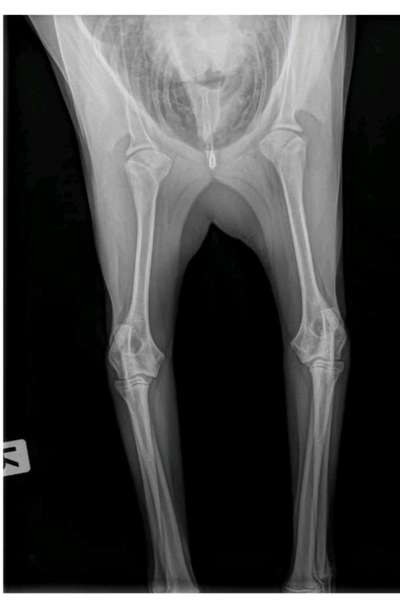

Hallo liebe Leute, Aufgrund mehrwöchiger Lahmheit vorne links bei unserem 6 Monatigen Hund (Japanspitz, eher kleine - mittelgroße Rasse) haben wir in einer Tierklinik ihn röntgen lassen und anschließend ins CT gegeben. Nun hat er laut Ärzten im Ellenbogen eine beidseitige OCD und soll zumindest auf der linken Seite operiert werden. Wir sind recht überfordert mit der Diagnose und wollen eine 2. Meinung noch einholen. Angehängt sind die Bilder. Unser Hund hatte keine Unfälle (natürlich ist er mal im Laufen auf glatten Boden daheim mal weggerutscht). Gassi sind wir immer nach der 5-10 Minutenregel pro Monat gegangen. Treppen wurde und wird er getragen. Kein wildes Spiel mit anderen Hunden. Er darf nicht allein auf die Couch. Essen bekam er Anfangs das HappyDog für Welpen, ab und zu bisschen Naturjoghurt und Buttermilch. Seit einer ganzen Weile erhält er aber nun das Welpenfutter mit Lamm von Tails and Tales. Das frisst er ohne Joghurt (das vorherige TroFu wollte er kaum noch essen, daher der Wechsel). Leckerlis bestehen, wenn, aus seinem Trockenfutter, weil er das sehr gern mag. Oder getrocknetes Lamm oder Pferd. Weil er vor einer Weile Giardien hatte bekommt er noch was zum Aufbau der gesunden Darmflora und hat inzwischen wieder guten Stuhlgang etc. Das Lahmen schwankt übrigens. Jetzt läuft er seit 2 Tagen recht gut ( Gassi ist schon seit Wochen nur an der Leine), aber das muss nichts heißen. In seiner Zuchtstätte gab es seit 20 Jahren nicht so einen Fall und ich glaube das auch. Sind hier Experten für OCD? Was habt ihr für Erfahrungen? Was sagt ihr zu unserem Befund? Macht eine OP Sinn in diesem Fall? LG Anna

Seine Hüfte ist okay?

Seine Hüfte ist ok, die Schultern auch.